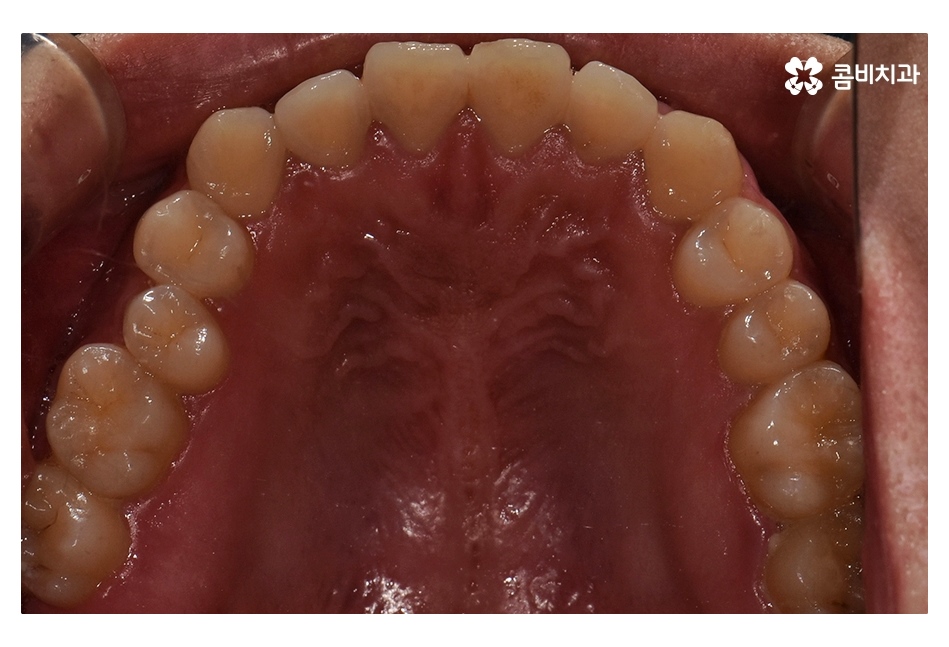

치아교정은 개인에 따라서 치료 기간이 달라지겠지만

위 환자분의 경우 수술과 병행되어 비발치 교정으로 진행되었기 때문에

약 1년 6개월 정도의 기간이 소요되었으며

교정 후 교합이 정상적으로 맞물리는 것을 확인할 수 있어요.